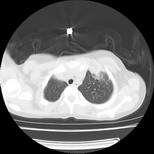

标题: PED3145:女,12岁,前期发热,咳嗽,无痰,CT右肺上叶实变 [打印本页]

标题: PED3145:女,12岁,前期发热,咳嗽,无痰,CT右肺上叶实变

女,12岁,前期发热,咳嗽,无痰,经头孢抗炎无效。ct右肺上叶实变影.5天后公布病理结果。以下是2010-2-13ct片